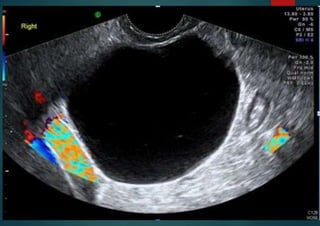

Serous cystadenoma

unilocular, regular walls, <10 cm